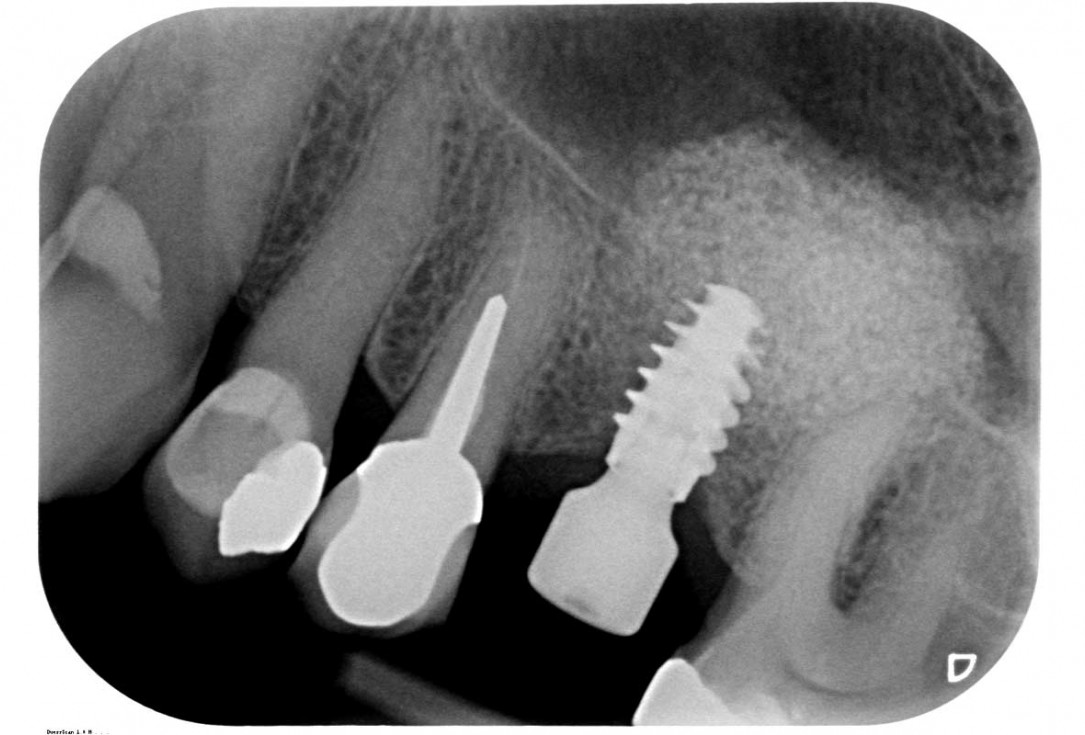

35/35 - X-ray follow-up at 8 months from the delivery of the crownMaxillary sinus cyst removal using the Crocodile Technique and subsequent lateral sinus lift - Dres. C. Scognamiglio and A. Perucchi